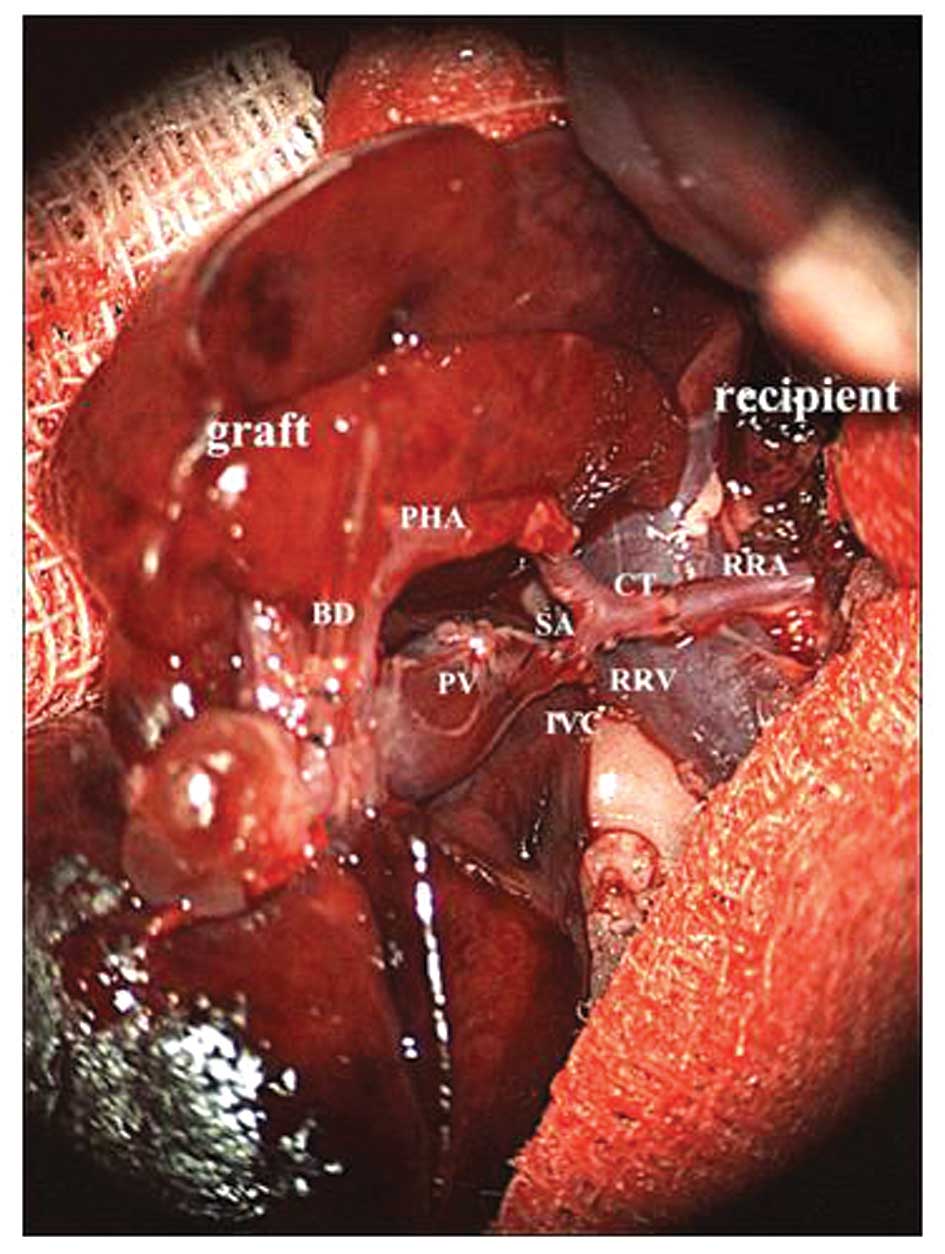

Liver transplant india, best liver transplant surgery. Liver transplant india dr. A. S. Soin has performed more than 1500 liver transplants and was awarded the padma shri in 2010 for pioneering the development of liver.

Liver most cancers signs and reasons mayo health center. Liver most cancers complete assessment covers symptoms, prognosis and treatment of liver cancer, including hepatocellular carcinoma. Liver most cancers hepatocellular carcinoma medlineplus. Get detailed information approximately liver cancer from the american cancer society. Liver most cancers symptoms & symptoms ctca. Learn about liver cancer signs. Although symptoms of liver most cancers may not appear in the early ranges, a few people may additionally experience weight loss, ache or jaundice. A liver transplant is recommended while someone’s liver now not functions appropriately enough to maintain them alive. A successful liver transplant is a lifesaving. Liver most cancers cancercenter. Also try. Liver cancer symptoms, signs, survival price, analysis. Liver most cancers is hard to diagnose as signs and signs are indistinct and nonspecific. Get statistics about liver cancer signs, remedy, levels, survival price.

Liver most cancers integrative treatment program ctca. Statistics on liver transplant, the tests required, locating a suit, difficulty, antirejection medications, and the followup vital. Liver statistics about the liver liver transplant india. Liver is the largest internal organ in the body. Liver does distinct essential capabilities. At liver transplant india you could get the all facts approximately human liver. Liver most cancers cancercenter. Online support institution for biliary atresia and other pediatric liver sicknesses and liver transplant.

signs of liver damage early signs and symptoms, causes & remedies. Our docs are right here to help you make sense of your liver most cancers. Liver most cancers hepatocellular carcinoma medlineplus. The most commonplace shape of liver cancer in adults is hepatocellular carcinoma. Find out about analysis, remedy and taking component in studies research. Liver households pediatric liver sickness, biliary atresia. On-line guide group for biliary atresia and different pediatric liver diseases and liver transplant. Symptoms of liver harm early signs and symptoms, reasons & treatments. 1857 related questions. Integrative liver cancer remedy. Ctca uses superior technologies and supportive care offerings that will help you better tolerate remedy and control facet outcomes. Liver transplant american liver foundation. I'd not keep out wish for it. If the cancer may be very advanced, there are probably metastases that received't be stricken by the transplant. Plus, the expecting an organ, if he's typical as a candidate, can be too lengthy for him. I hope he. Accelerated liver enzymes reasons, treatment, and more info. Find out about viable reasons of improved liver enzymes, what it is able to imply for you, and what ability remedies are available.

Liver cancer evaluation american cancer society. Publish liver transplant. Locate outcomes. Discover reference associated content material. A liver transplant is an operation that replaces a affected person's diseased liver with a whole or partial healthful liver from any other individual. This text explains the. Liver transplant about mayo health facility. Liver transplant is a remedy choice for human beings with liver failure whose situation cannot be managed other with treatments and for some humans with liver most cancers. Liver cancer transplant yahoo solutions outcomes. Liver transplant india dr. A. S. Soin has achieved more than 1500 liver transplants and become offered the padma shri in 2010 for pioneering the development of liver. Liver transplant india, fine liver transplant surgical operation. Liver transplant india dr. A. S. Soin has accomplished greater than 1500 liver transplants and was presented the padma shri in 2010 for pioneering the improvement of liver. Liver transplant find out approximately surgical procedure headaches. Information on liver transplant, the exams required, locating a fit, hardship, antirejection medications, and the followup necessary. Liver transplant india official web site. Greater classes community & assist, survivors, the ctca blog. Liver transplant discover about surgery complications. Explore extra approximately symptoms of liver damage now. Browse beneficial informations right here.

Liver most cancers causes, survival price, tumor sorts, and extra. Webmd explains the fundamentals of liver cancer. What's liver most cancers? The liver constantly filters blood that circulates through the frame, changing vitamins and. Liver cancer survival quotes cancer of the liver survival quotes. No, this youngster would be denied to receive a transplant if the most cancers has unfold to different areas or another vicinity despatched the most cancers to the liver. Once the most cancers has unfold, transplant is not an choice due to the fact that it'd no longer trade such things as. Liver most cancers integrative treatment application ctca. Integrative liver most cancers remedy. Ctca uses advanced technology and supportive care offerings to help you better tolerate treatment and control aspect results. Liver most cancers survival fees most cancers of the liver survival. · the numbers below come from the countrywide most cancers institute's surveillance, epidemiology, and give up outcomes (seer) database, and are primarily based on sufferers who had been. Transplant surgical treatment liver transplant. Richard, i let you very a whole lot as i'm from the dfw place and feature lived right here all my 52 years! First, i need to mention i am sorry. My daughter has had a kidney transplant and we've handled the transplant system in each dallas and toes. Put up liver transplant reference. Cancercenter has been visited with the aid of 10k+ customers in the past month.